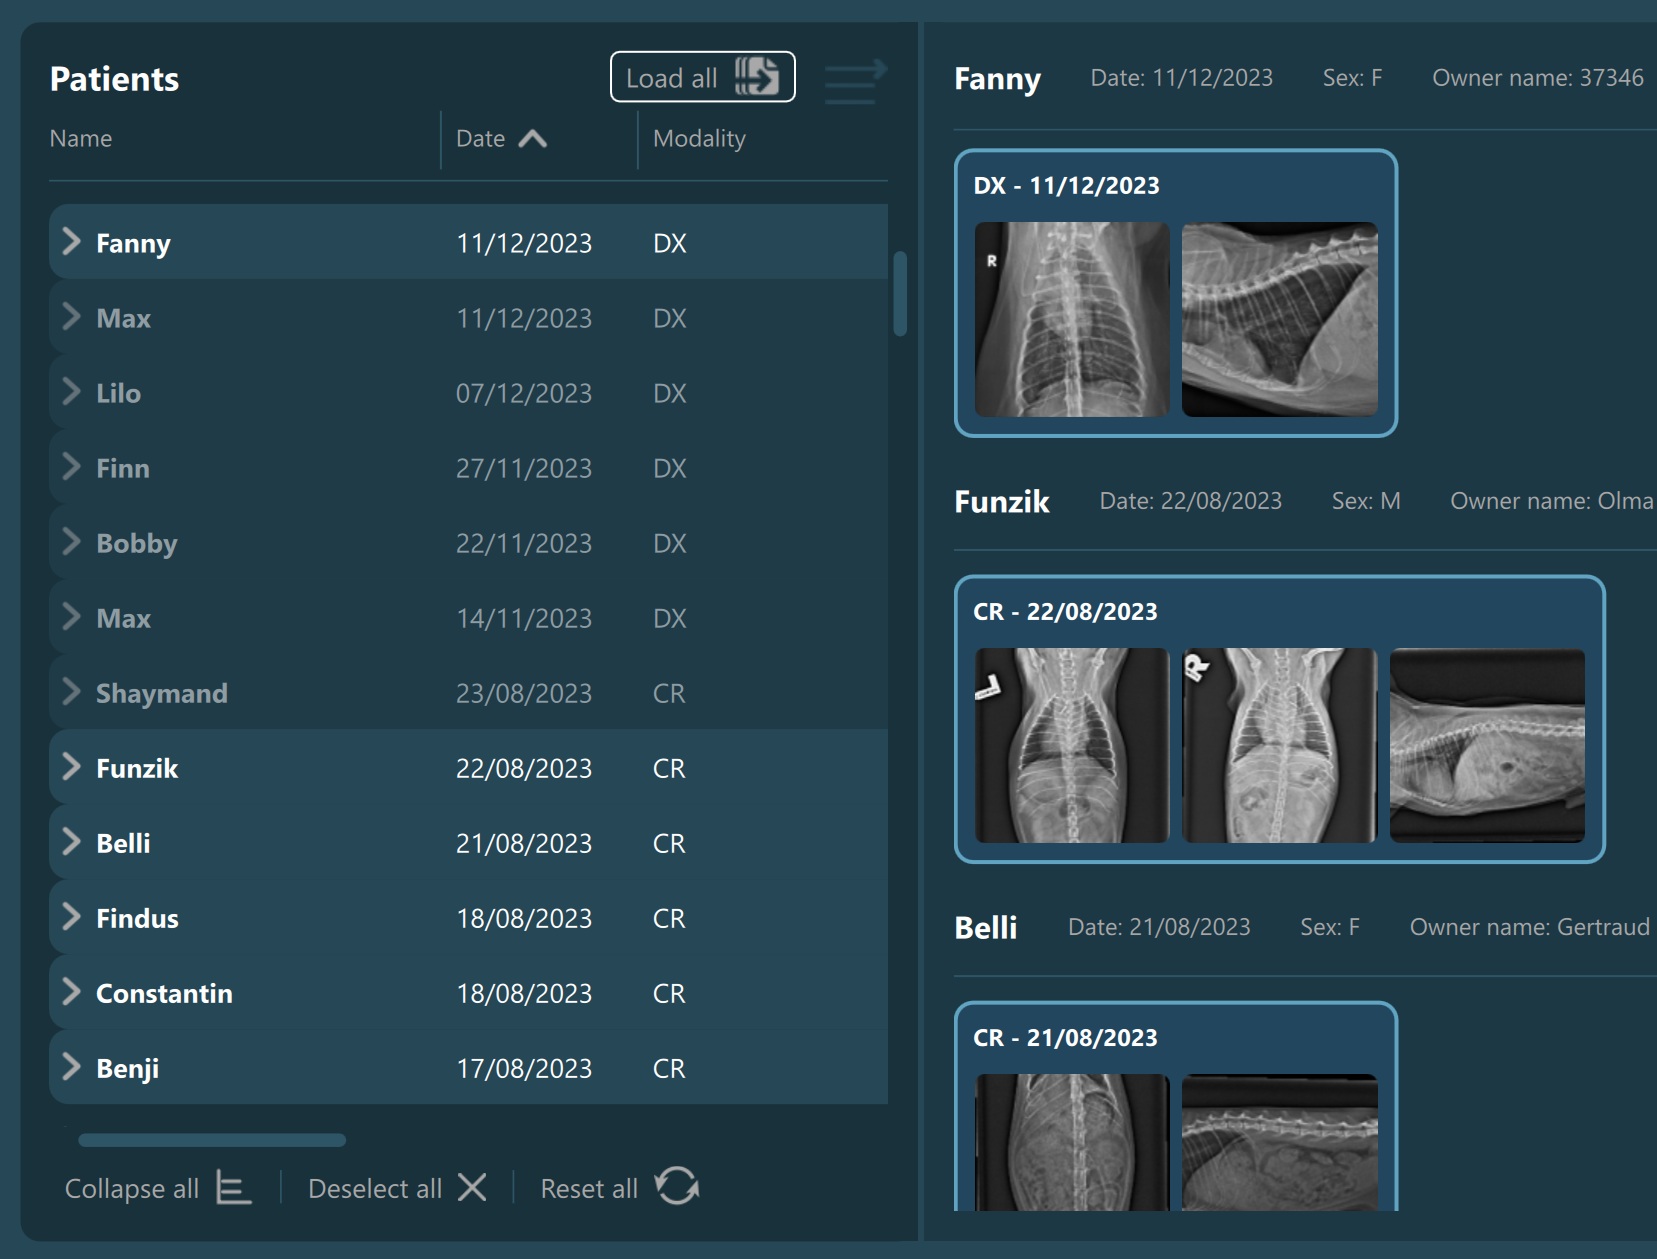

The Study List is located on the left side of the Study Browser window. All studies or patients (depending on the active mode) from the selected server will be displayed in the study list, based on the configuration of the DICOM servers.

Expand an item in the Study List by pressing the arrow next to the its name, which reveals its contents based on the DICOM hierarchy in the Study Browser.

Selecting a patient, study, or series from the Study List opens them and their contents in the Preview Pane, located on the right side of the Study Browser window. In the Preview Pane, the items are separated into sections based on their patient information.

The heading of each section shows the patient name, the latest related study date, patient sex, and owner name. Studies are shown as image groups containing the series as image previews. Each study is highlighted by its modality and date. To view the series description of each series, hover over the desired image preview.

The top right corner of the Preview Pane offers the users the ability to switch the thumbnail preview between unified or keeping the original aspect ratio of the image.

Similar to the selection in the Study List, users have the ability to select patients, studies, or individual series. A highlighted selection in the Preview Pane indicates the active selection in the Study List.

The Preview Pane can also be used to extend or narrow down the selection from the Study List. To select/deselect items in the Preview Pane simply press on them with the mouse.